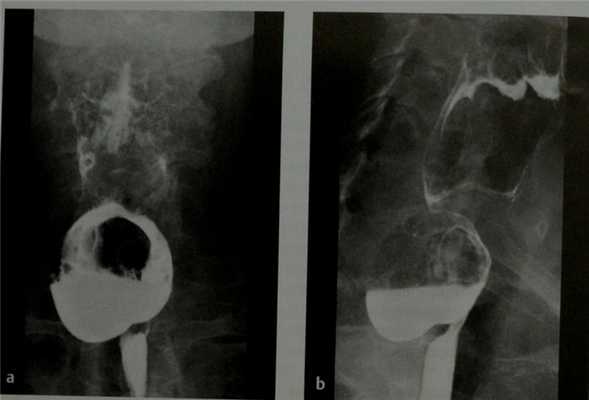

а, b Дивертикул Ценкера большого размера. Рентгенография в прямой (а) и боковой (b) проекциях с контрастированием бариевой взвесью. На боковой проекции визуализируется сужение на уровне перстневидно-глоточной мышцы.

• Дивертикул Ценкера выглядит как заполненное контрастом мешковидное выпячивание задней стенки шейного сегмента пищевода:

о Располагается сразу же над перстневидно-глоточной мышцей на уровне 5-6 шейных позвонков

о Сужение просвета в области глоточно-пищеводного перехода за счет давления извне

о Крупные дивертикулы могут выбухать латерально (влево) или приводить к сдавливанию шейного сегмента пищевода

- На снимках в боковой проекции визуализируется выпячивание задней поверхности пищевода, достигающее при больших дивертикулах уровня средостения;

- Шейка дивертикула визуализируется выше анатомического сужения пищевода перстневидно-глоточной мышцей;